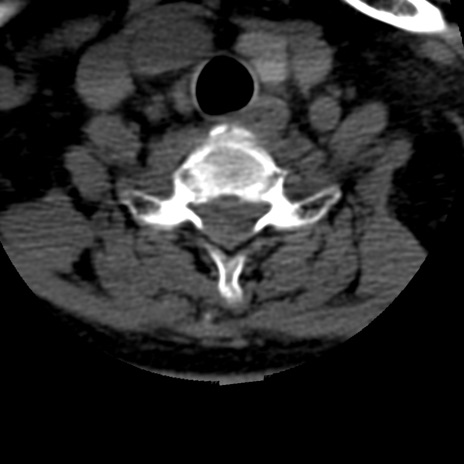

症例50 頚椎CT(横断像)

頚椎CT